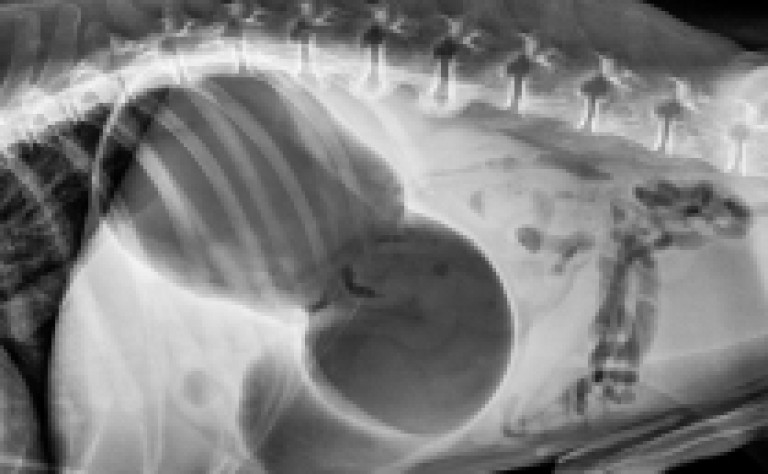

Finalement, le STDE est confirmé ou non grâce à une radio.

La torsion de l’estomac se produit lorsque l’estomac d’un chien se remplit de gaz, de fluide ou d'aliments et se tord sur lui-même.

Lors de la dilatation, l'estomac peut occuper plus de la moitié de la cavité abdominale !

La dilatation est très douloureuse et perturbe le fonctionnement des fonctions vitales telles que la respiration et la circulation du sang.

La torsion du tractus digestif empêche non seulement le gaz de s'échapper, mais il coupe également la circulation sanguine vers certains tissus.